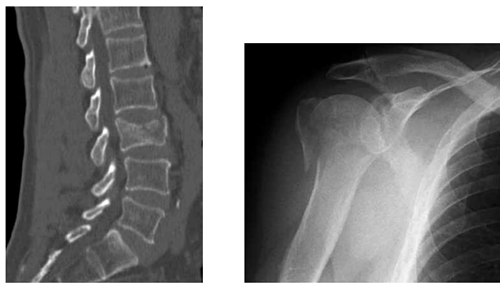

Uma paciente de 89 anos vem a consultório com histórico de queda após tropeçar no tapete de sua casa, há 10 meses, e ao escorregar no piso de seu banheiro, há 1 semana. Não tem antecedentes mórbidos. Relata somente que faz uso de alendronato 70 mg/semana, há 2 anos. Ela trouxe as radiografias realizadas por ocasião desses dois traumas. Seus exames laboratoriais estão normais.

Enunciado 4448839-1

Em função desse achado, foi realizada uma análise por meio da ferramenta Frax 2.0.

Enunciado 4448839-2

Diante do exposto, recomenda-se como tratamento para a paciente